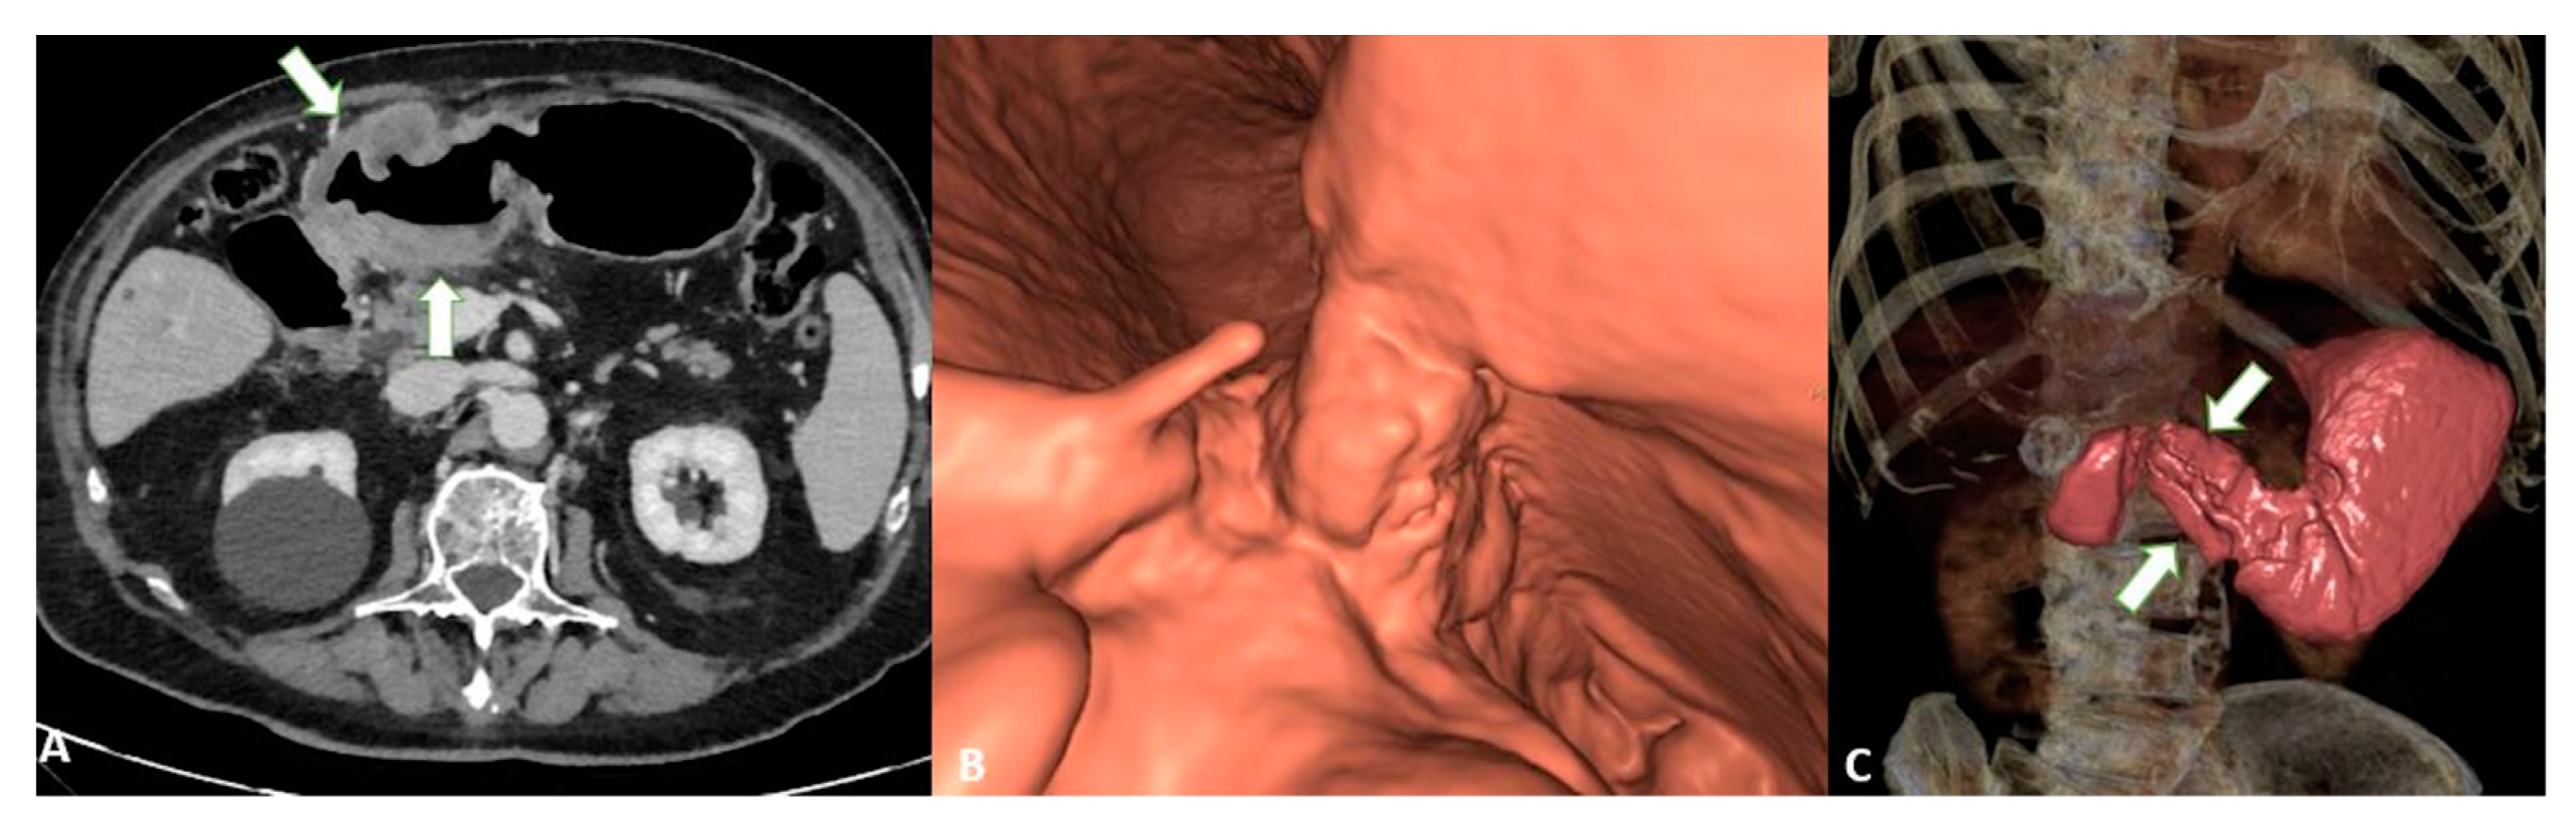

The added value of MPR combined with VG can increase the overall accuracy (from 73 to 89%) thanks to its ability to better assess invasion (Figure 6) [30].

Figure 6.

T4a gastric cancer in a 53-year-old female patient. (A) Axial 2D image in the portal venous phase with distension of the gastric lumen with air shows a bulky circumferential tumor (white arrows) of the low body of the stomach and of the gastric antrum with ulcerations; (B) Virtual gastroscopy delineates a lesion protruding in the lumen of the stomach; (C) Computed tomography gastrography shows a mucosal irregularity (white arrows) with a reduction of the lumen of the stomach.

To confirm this hypothesis, other studies have reported that VG can enhance the recognition of GC, especially EGC [31]. In support of these data, it has been demonstrated [32] that VG can increase the overall performance compared to axial images alone in detecting EGC with sensitivity and specificity levels of 91.9% and 74% and 62.9% and 82.9%, respectively (Figure 7).

Figure 7.

T3 gastric cancer in a 68-year-old female patient. Contrast enhanced CT with gastric distension using air. (A) Axial 2D image and (B) Coronal 2D image in the portal venous phase with distension of the gastric lumen with air showing a semicircumferential tumor (white arrows) of the low body of the stomach with ulcerations.

Similarly, in a study involving 106 patients, GC was found to be easier to detect with VG (87% vs. 98%). The authors demonstrated that the accuracy was significantly higher when using VG compared with axial images (84% and 77%, respectively). On the other hand, the authors reported no significant difference in N staging, with overall accuracy levels of 62% and 64% for axial images compared to VG, respectively [24].